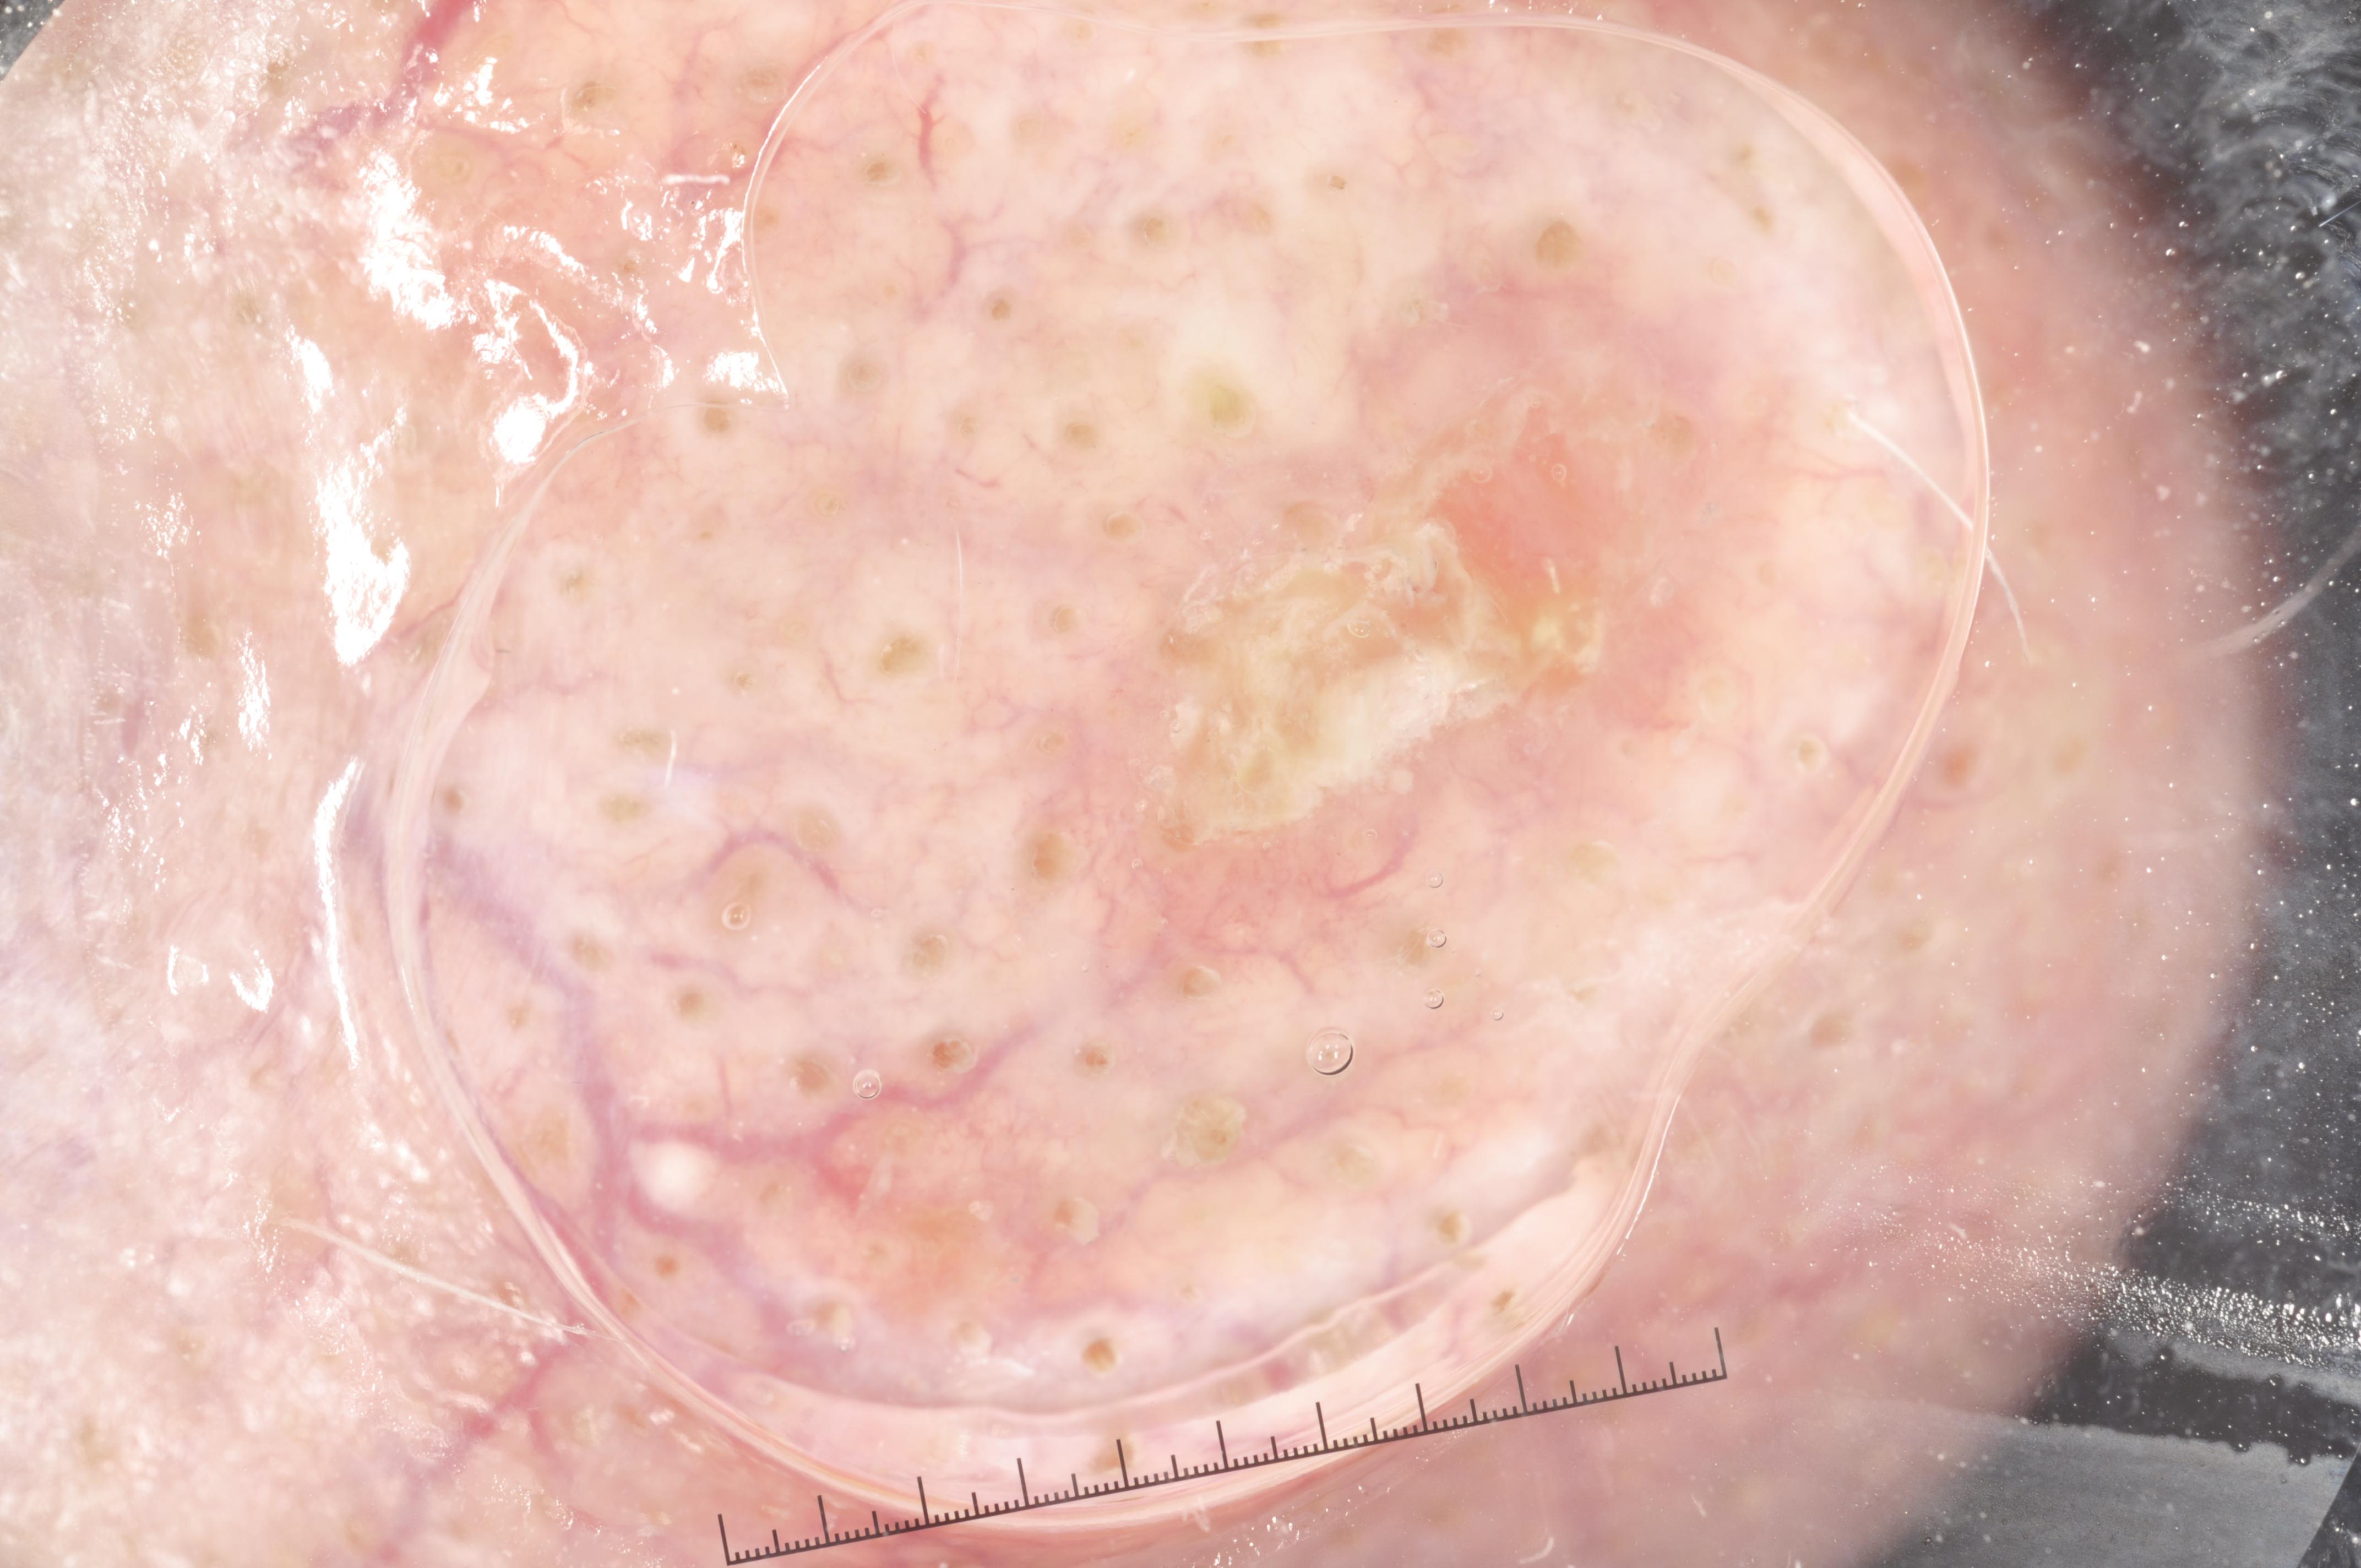

{

"age_approx": 65,

"anatom_site_general": "upper extremity",

"concomitant_biopsy": true,

"dermoscopic_type": "contact non-polarized",

"diagnosis_1": "Malignant",

"diagnosis_2": "Malignant melanocytic proliferations (Melanoma)",

"diagnosis_3": "Melanoma Invasive",

"diagnosis_4": "Melanoma Invasive, Associated with a nevus",

"diagnosis_confirm_type": "histopathology",

"image_type": "dermoscopic",

"lesion_id": "IL_6937786",

"melanocytic": true,

"sex": "male"